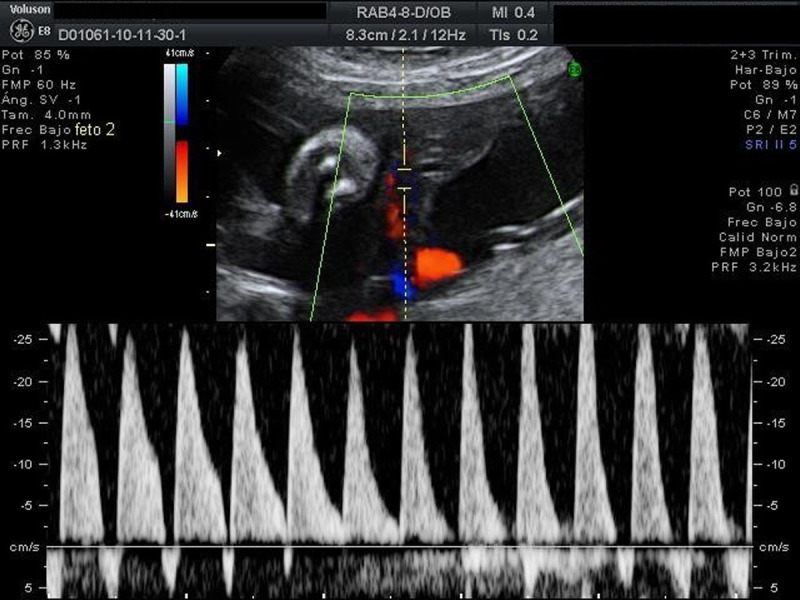

Selective fetal growth restriction (sFGR) is a severe condition that complicates 10% to 15% of all monochorionic diamniotic (MCDA) twin pregnancies. Pregnancies complicated with sFGR are at high risk of intrauterine demise or adverse perinatal outcome for the twins. Three clinical types have been described according to the umbilical artery (UA) Doppler pattern observed in the smaller twin: type I, when the UA Doppler is normal; type II, when there is persistent absent or reversed end-diastolic blood flow in the UA Doppler; and type III, when there is intermittent absent and/or reversed end-diastolic blood flow in the UA Doppler. Clinical evolution and management options mainly depend on the type of sFGR. Type I is usually associated with a good prognosis and is managed conservatively. There is no consensus on the management of types II and III, but in earlier and more severe presentations, fetal interventions such as selective laser photocoagulation of placental anastomoses or selective fetal cord occlusion of the smaller twin may be considered. This review aims to provide updated information about the diagnosis, evaluation, follow-up, and management of sFGR in MCDA twin pregnancies.